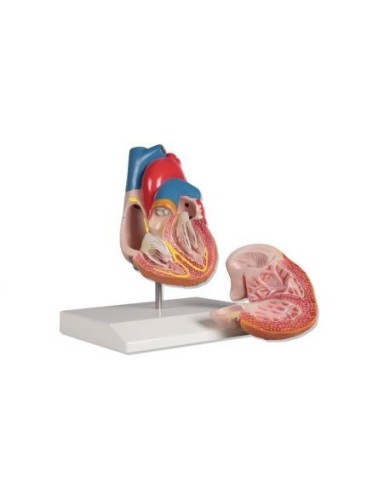

Modello di cuore di alta qualità scomponibile in 5 parti

Modello di cuore di alta qualità scomponibile in 5 parti

La parete anteriore del cuore è staccabile per poter vedere i ventricoli.

Modello anatomico di cuore, ingrandito 2 volte, su cavalletto